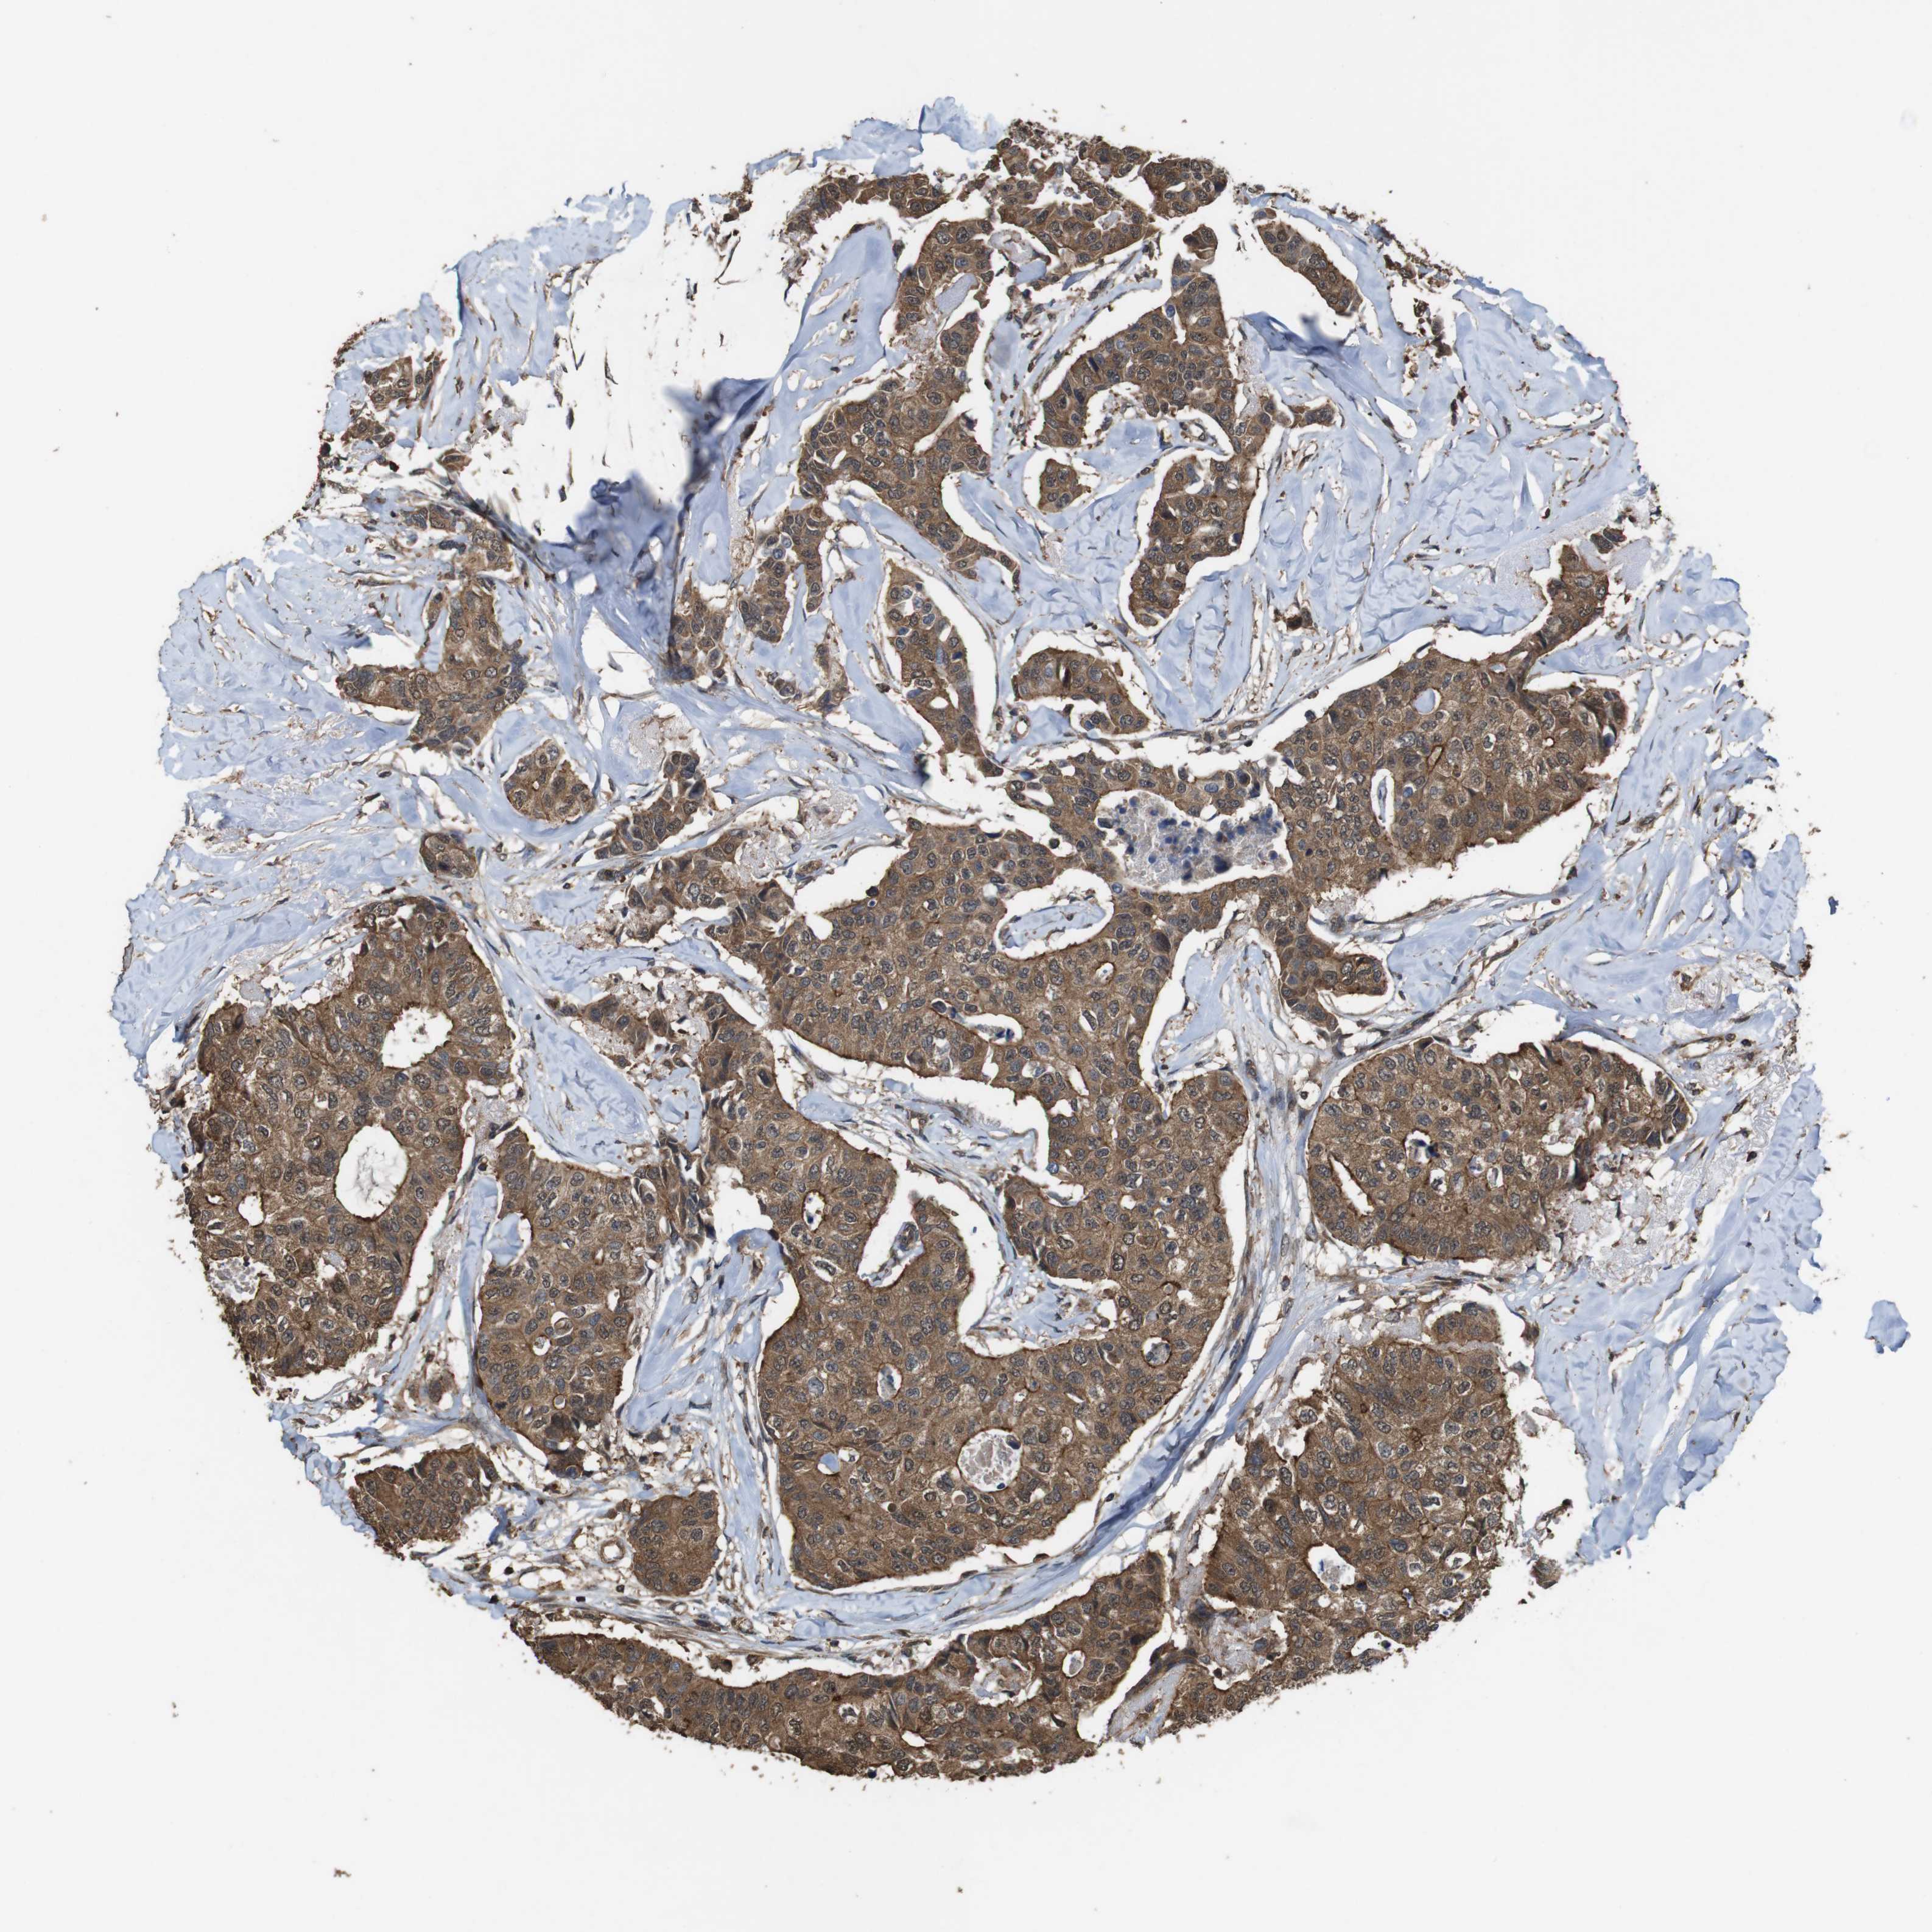

CANCER BREAST CANCER Show tissue menu

BRCA TCGA BRCA VALIDATION PROTEIN EXPRESSION

ANTIBODIES

AND

VALIDATION